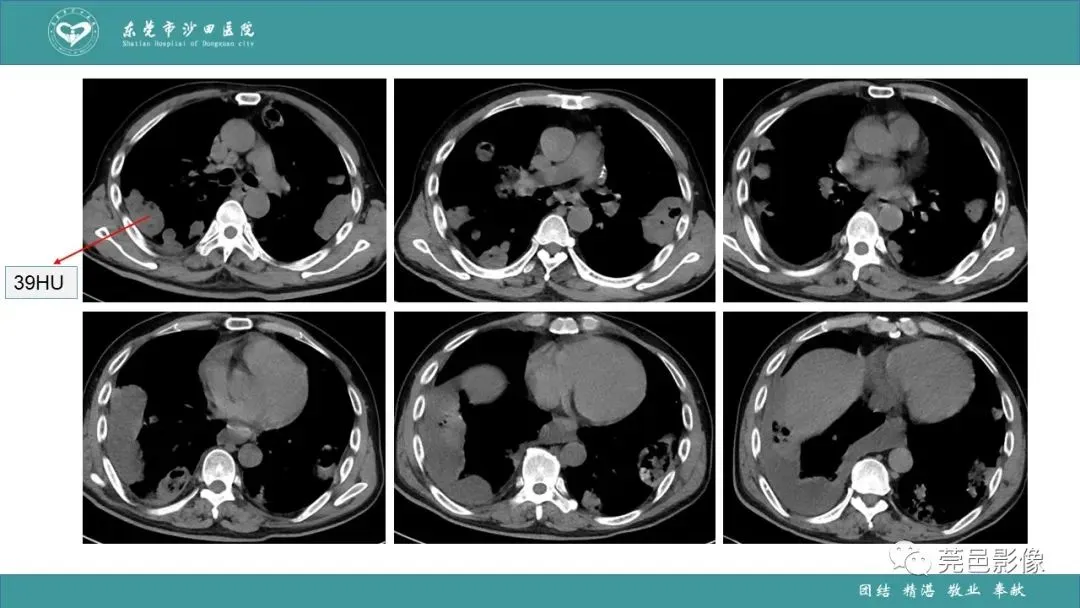

>课件 | 肺炎克雷伯杆菌肺炎影像学诊断与鉴别诊断

课件 | 肺炎克雷伯杆菌肺炎影像学诊断与鉴别诊断